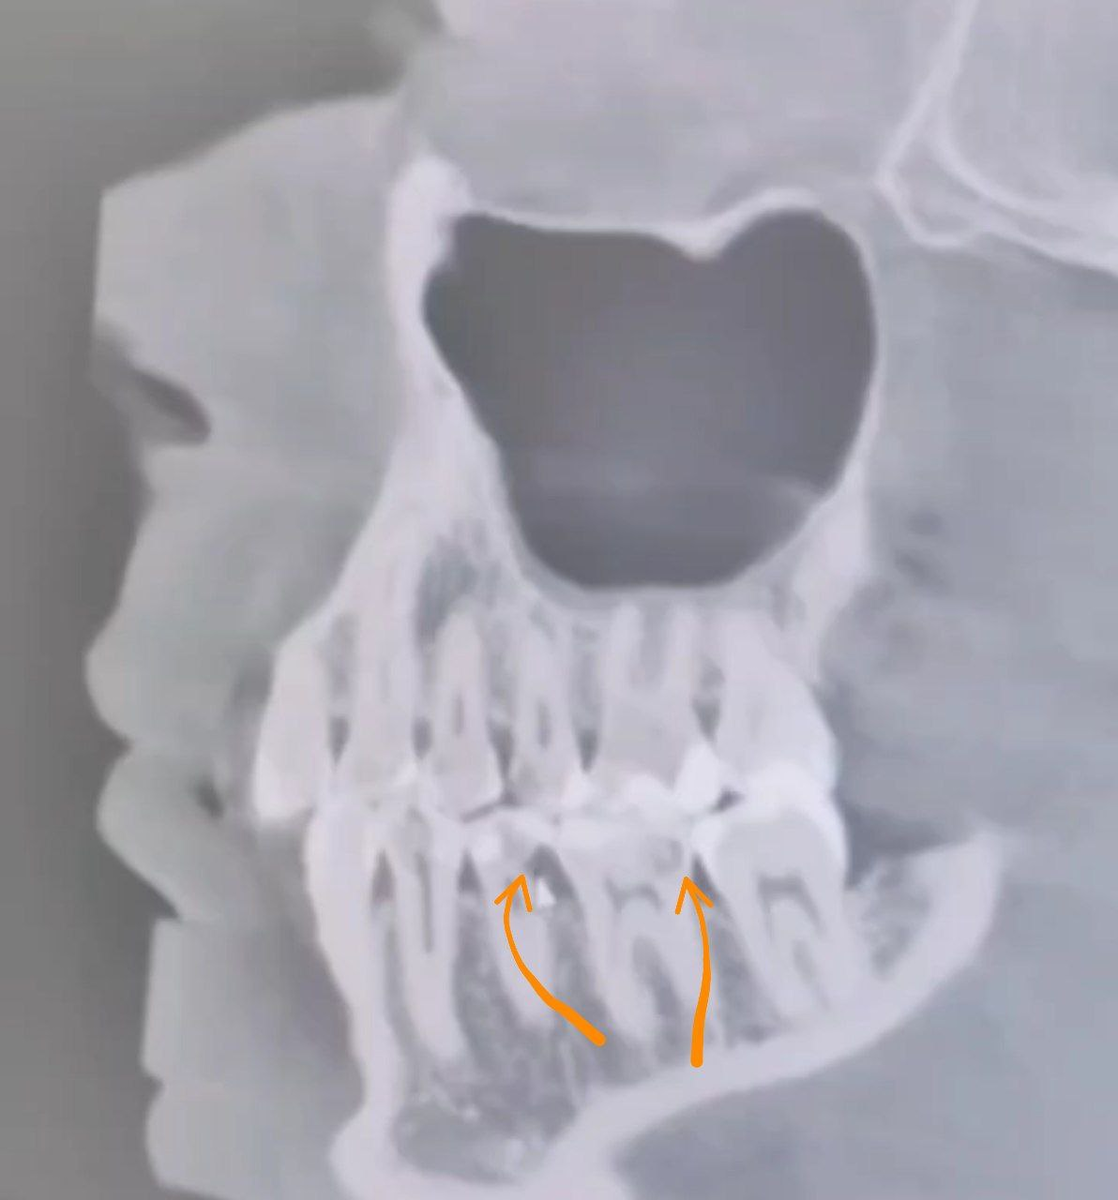

🚩Вак ΠΊΠ°ΠΊ ΠΆΠ΅ выглядит кариСс Π½Π° снимкС?

πŸ”΄ΠΠ° КВ ΠΊΠ°Ρ€ΠΈΠΎΠ·Π½Ρ‹Π΅ полости ΠΎΡ‚Ρ‡Π΅Ρ‚Π»ΠΈΠ²ΠΎ Π²ΠΈΠ΄Π½Ρ‹.

Они ΠΏΡ€ΠΎΡΠ²Π»ΡΡŽΡ‚ΡΡ, ΠΊΠ°ΠΊ Π·Π°Ρ‚Π΅ΠΌΠ½Π΅Π½Π½Ρ‹Π΅ пятна, ΡˆΡ‚Ρ€ΠΈΡ…ΠΈ ΠΈΠ»ΠΈ полосы.

А Π²ΠΎΡ‚ здоровая костная Ρ‚ΠΊΠ°Π½ΡŒ, Π½Π°ΠΎΠ±ΠΎΡ€ΠΎΡ‚, Ρ…ΠΎΡ€ΠΎΡˆΠΎ ΠΎΡ‚Ρ€Π°ΠΆΠ°Π΅Ρ‚ ΠΈΠ·Π»ΡƒΡ‡Π΅Π½ΠΈΠ΅, поэтому ΠΈΠΌΠ΅Π΅Ρ‚ Π±Π΅Π»Ρ‹ΠΉ Ρ†Π²Π΅Ρ‚ ΠΈ выглядит ΠΏΠ»ΠΎΡ‚Π½ΠΎΠΉ, Π² ΠΎΡ‚Π»ΠΈΡ‡ΠΈΠ΅ ΠΎΡ‚ размягчСнных кариСсом Ρ‚ΠΊΠ°Π½Π΅ΠΉ, ΠΏΡ€ΠΎΠΏΡƒΡΠΊΠ°ΡŽΡ‰ΠΈΡ… Π»ΡƒΡ‡ΠΈ.

ΠšΠ°Ρ€ΠΈΠ΅Ρ Π²ΠΈΠ΄Π΅Π½ Π½Π° Ρ€Π΅Π½Ρ‚Π³Π΅Π½ снимкС ΠΈ Π½Π° КВ, Π½ΠΎ ΠΏΠ°Ρ€Π°Π»Π»Π΅Π»ΡŒΠ½ΠΎ диагностику двумя ΠΌΠ΅Ρ‚ΠΎΠ΄Π°ΠΌΠΈ проводят Ρ€Π΅Π΄ΠΊΠΎ.